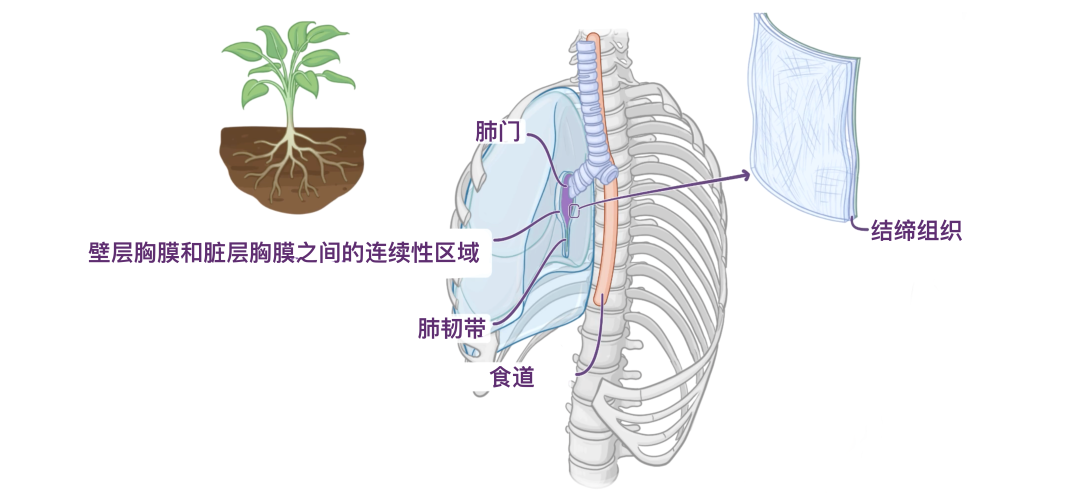

这些根通过称为肺门的通道进入和离开肺部,类似于植物的根进入地下的方式。肺门内侧,朝向中央纵隔,肺根被包围在胸膜壁层和脏层之间的连续区域内。在肺根下方,壁层胸膜和脏层胸膜之间的这种连续性形成肺韧带,在肺和纵隔之间延伸,直接位于食道之前。肺韧带由双层胸膜组成,中间被少量结缔组织隔开。